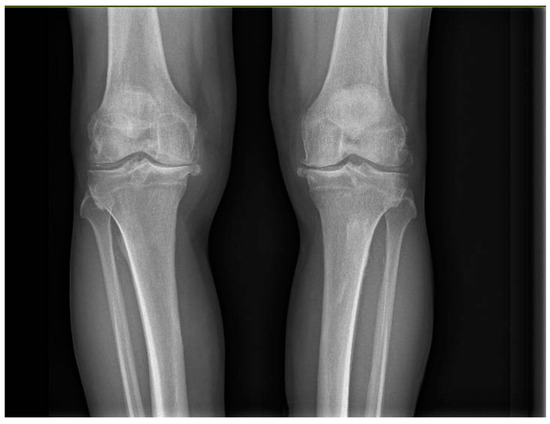

Antibiotic prophylaxis with cefazolin was used. All patients underwent radiographs (Figure 2) in the immediate postoperative period.

Figure 2. Postoperative radiography of bilateral total knee arthroplasty.